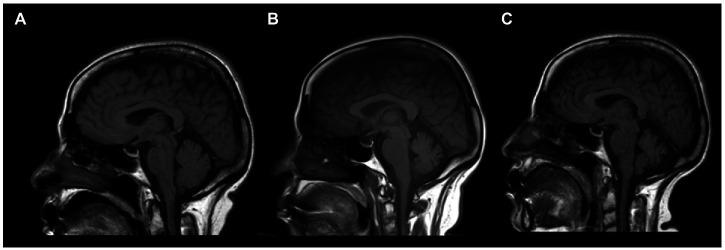

Including our case, 36 cases of anti-mGluR1 encephalitis (19 males, median age 52.5 years, 11.1% pediatric cases) have been reported. The most common clinical manifestations are ataxia, dysarthria, and nystagmus. Initial imaging was normal in 44.4% of patients; however, 75% of patients showed abnormality later in the disease course. The first-line therapy options include glucocorticoids, intravenous immunoglobulin, and plasma exchange. Rituximab is the most commonly used second-line treatment. Complete remission was achieved in only 22.2% of patients, and 61.8% were disabled by the end of their course.

包括我们的病例在内,共报道了36例抗mGluR1脑炎(19例男性,中位年龄52.5岁,11.1%为儿科病例)。最常见的临床表现为共济失调、构音障碍和眼球震颤。44.4%的患者初始影像学检查正常;然而,75%的患者在病程后期出现异常。一线治疗方案包括糖皮质激素、静脉注射免疫球蛋白和血浆置换。利妥昔单抗是最常用的二线治疗药物。仅22.2%的患者实现了完全缓解,61.8%的患者在病程结束时出现残疾。